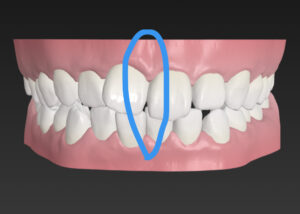

歯並びガタガタの そうせい を気にして

マウスピース矯正希望で来院

今回は しょうきゅうし は

非抜歯で計画

この歯並びが治る原理は

出っ歯🟰歯と歯の間を少し削り

スキマを作って歯をキレイに整列

上下の せいちゅう のズレ

皆様から見て右側に

Ⅲ級ゴムをかけて矯正